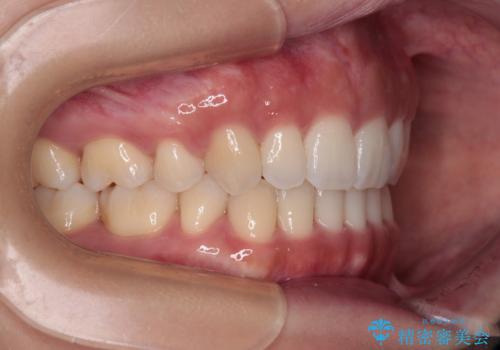

舌の突出癖を改善するためのトレーニングをしっかりと行っていただいたことで、比較的スムーズに治療を進めることができました。

口元の突出感もしっかりと改善することができました。